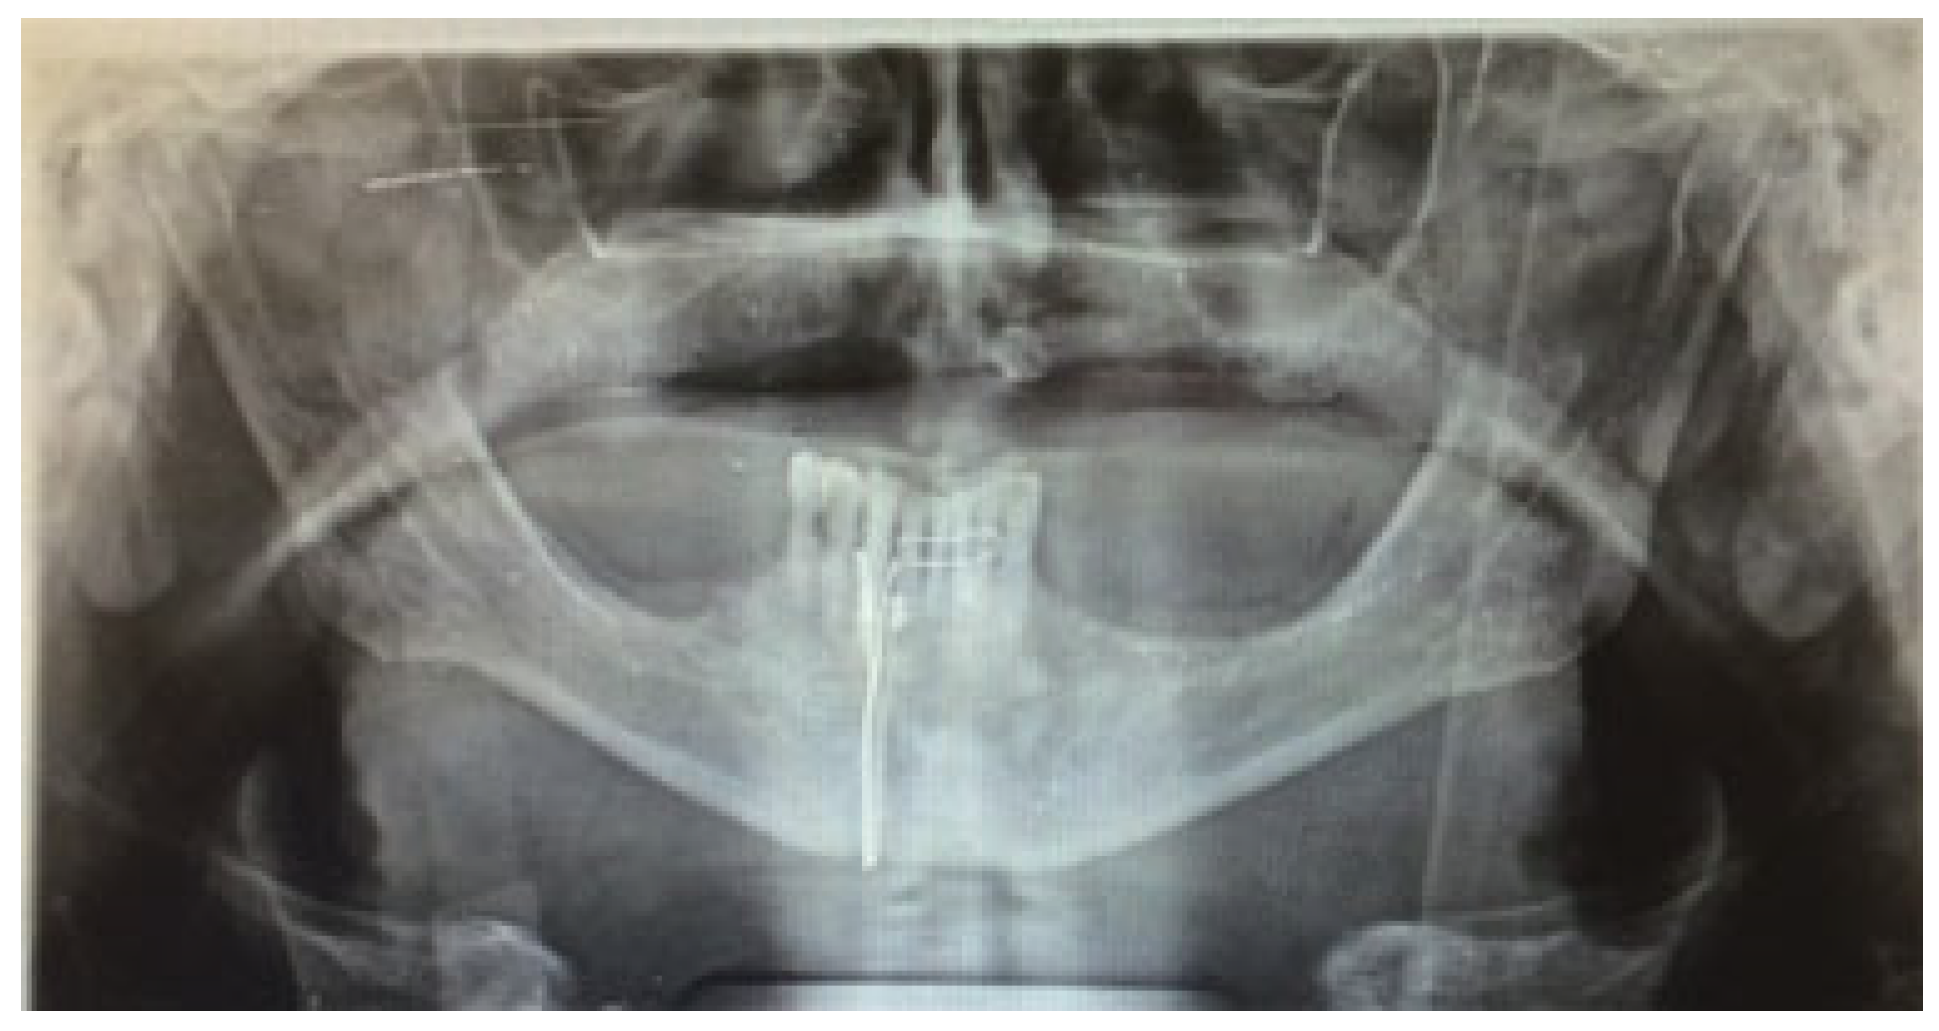

2.1. Case 1

2.2. Case 2